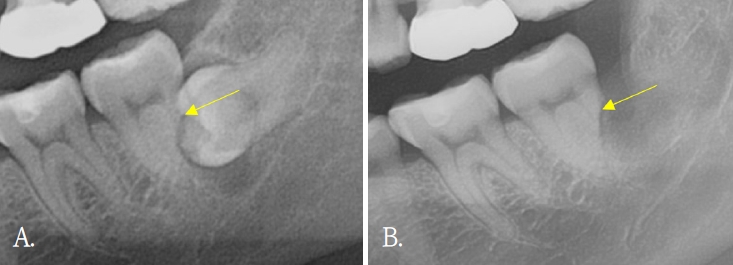

Clinical trial of platelet rich fibrin insertion for exposed dental pulp of second molar associated with impacted third molar: A pilot study

Yeeun Jo, Sanghuem Cho, Woong Nam

J Korean Dent Assoc.

2025;63(9):298-303. Published online September 30, 2025

DOI:

https://doi.org/10.22974/jkda.2025.63.9.003